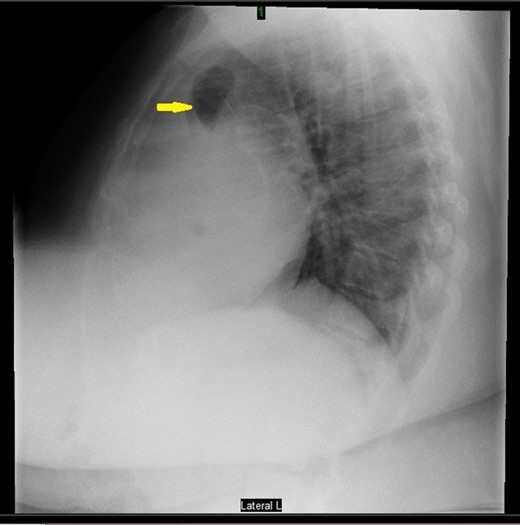

Prior to the surgery patient had symptoms of mild dyspnea, vague abdominal discomfort and an initial evaluation with Chest X Ray revealed bowel gas pattern in the right hemithorax (Fig. 1). A subsequent CAT scan thorax and abdomen revealed a right-sided large morgagni diaphragmatic hernia containing omentum and portion of the transverse colon (Fig. 2). Patient elected to undergo Laparoscopic sleeve gastrectomy and concomitant morgagni diaphragmatic hernia repair. Abdomen was explored laparoscopically which revealed a right sided morgagni diaphragmatic hernia with defect size about 8 × 4 cm, containing omentum, transverse colon and part of the falciform ligament. Contents were reduced successfully taking care not to injure the bowel, falciform ligament partially dissected. A sleeve gastrectomy done. Then the hernial defect was closed primarily by interrupted non absorbable sutures. The closure was then reinforced with a sublay ventralight mesh which was secured using transfascial fixation sutures and with tackers (Fig. 3). The post operative course was unremarkable and the patient was discharged on post operative Day 2 with normal chest X-ray (Fig. 4). At 2 months after surgery the patient was doing well and tolerating solid and liquid diet and no more dyspnea nor GI symptoms.

CAT scan thorax and abdomen revealed a right-sided large morgagni diaphragmatic hernia.